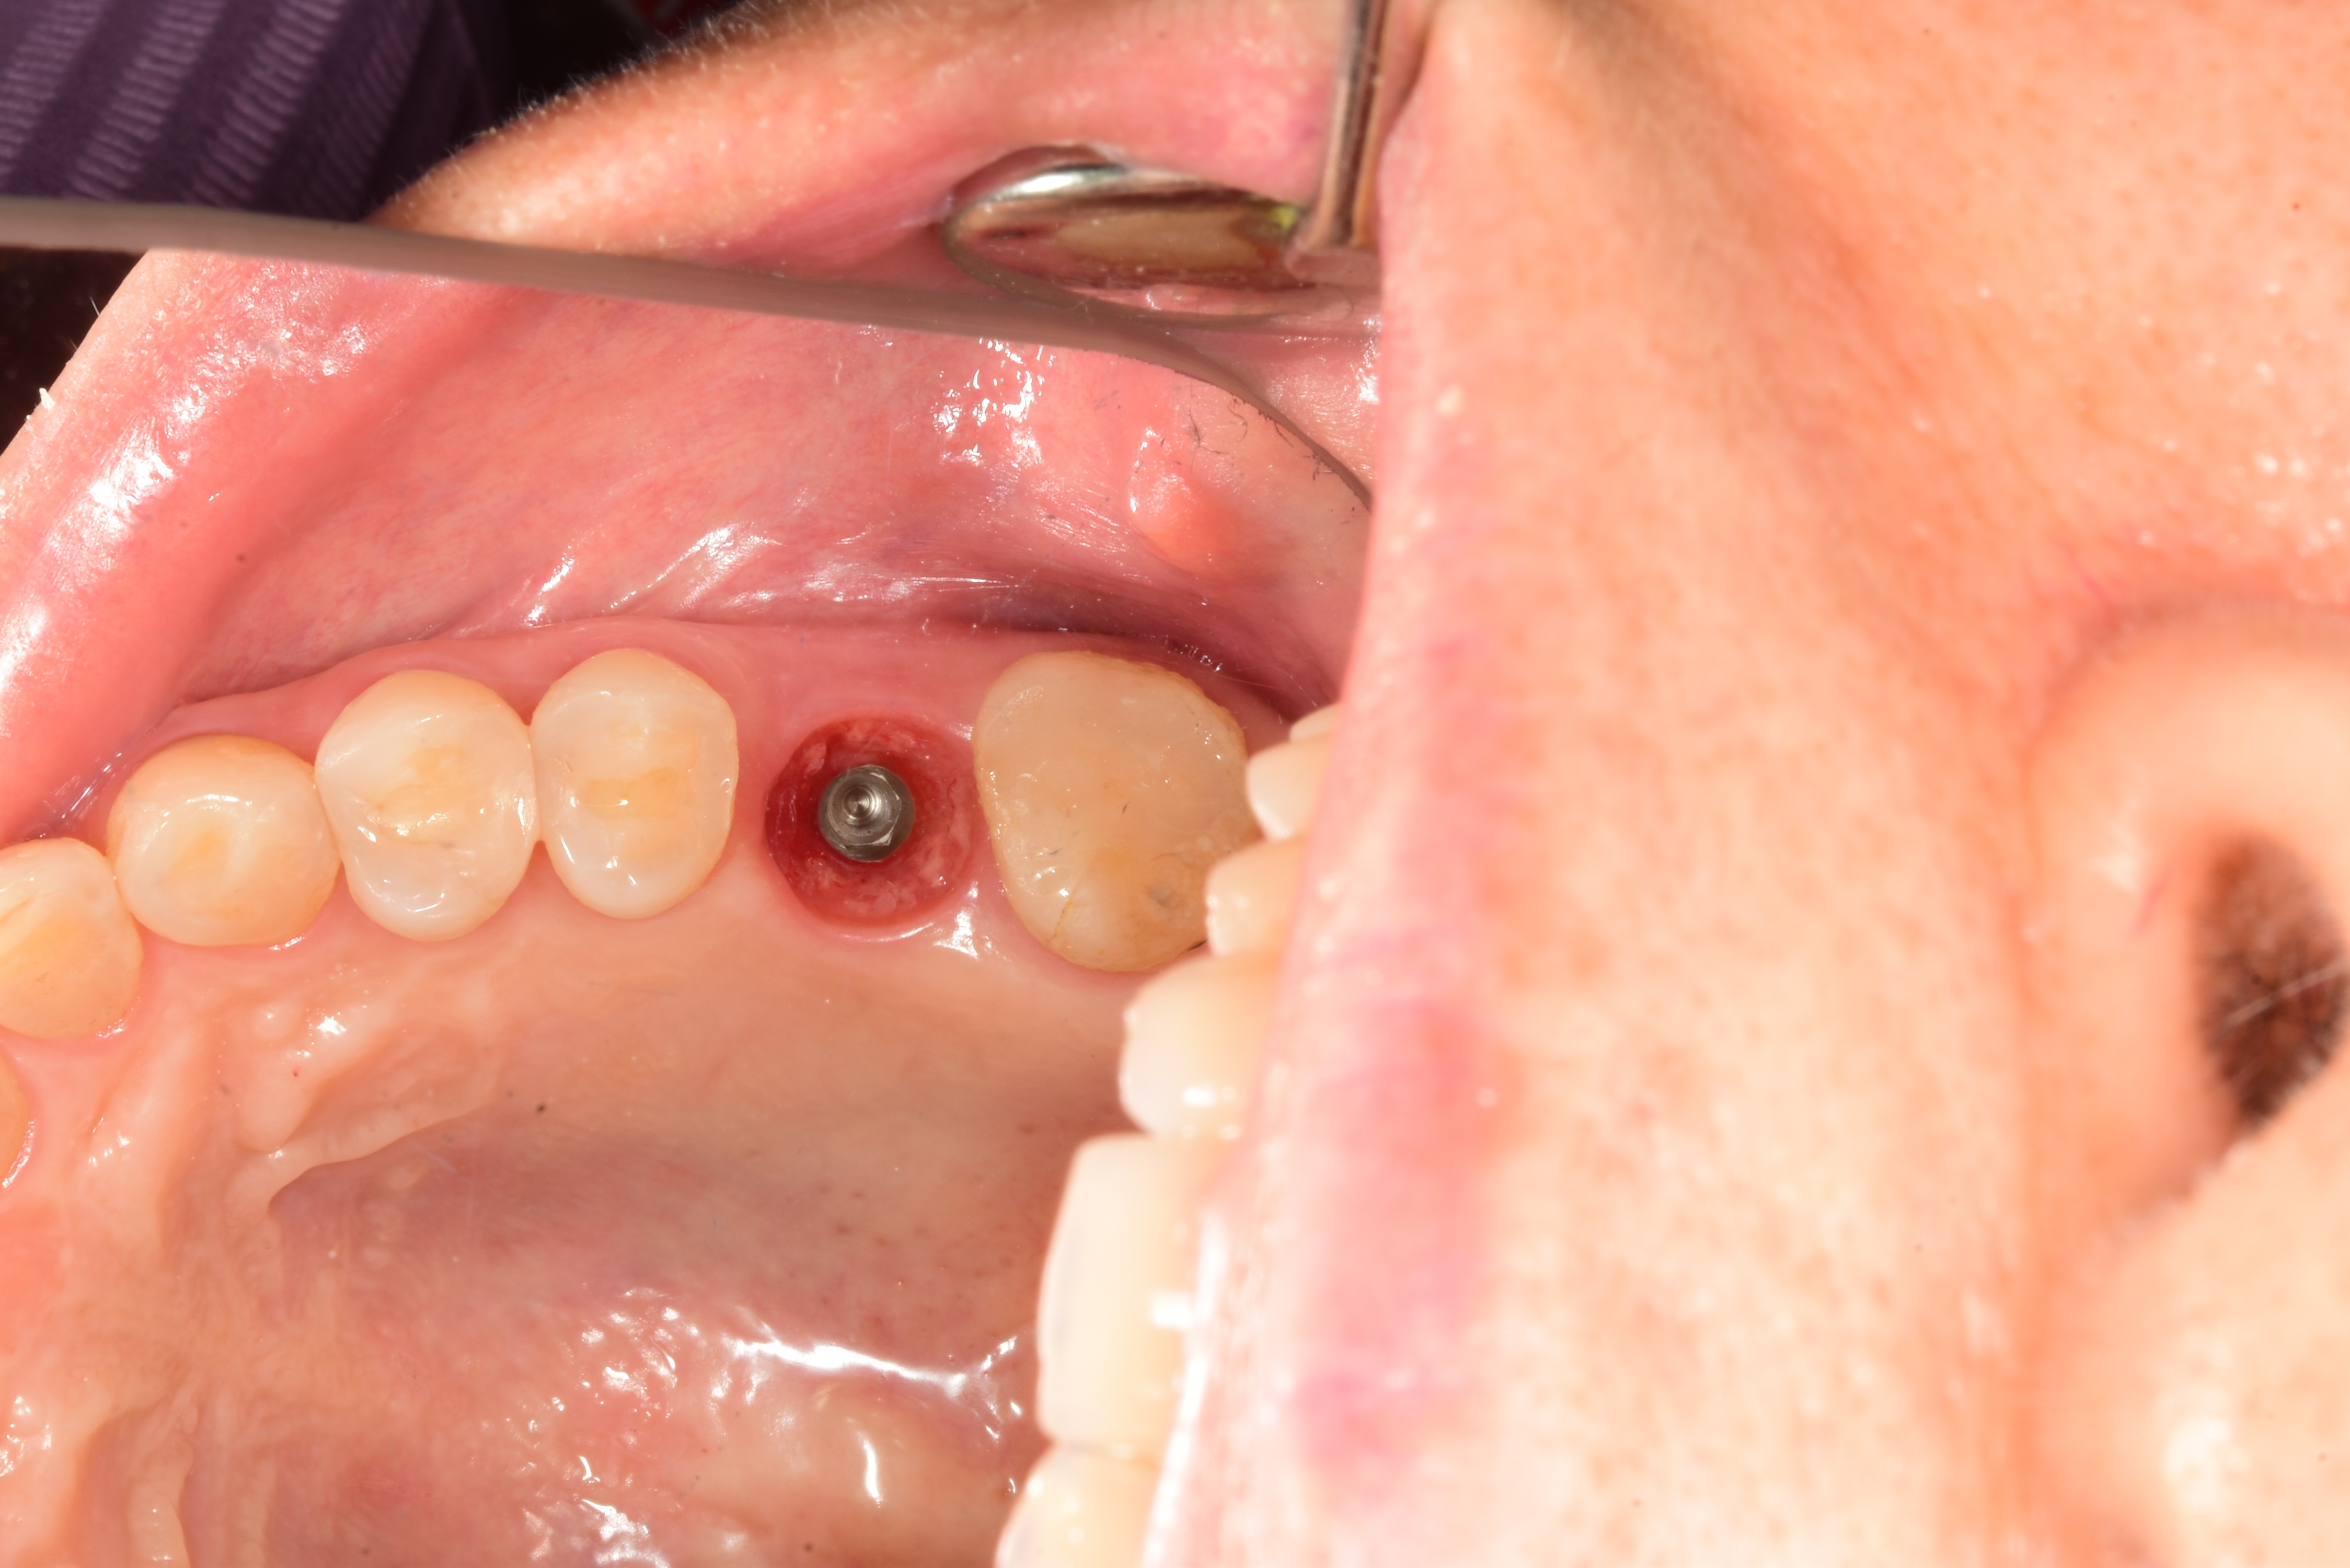

案例三

立即拔除牙根不好的牙齒

立即植入植體

鎖上癒合螺帽

2-3個月癒合,7-10天完成假牙 ,試戴、調整咬合高度並鎖上,封填,完成